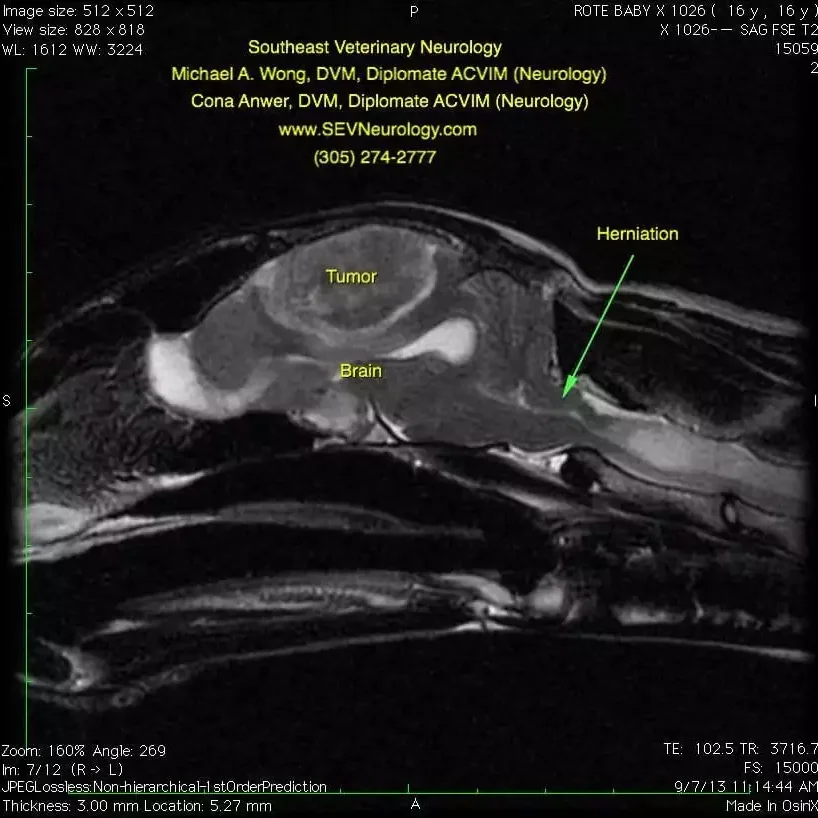

This second image is a T1 weighted sagittal image of Baby’s head. Contrast agent has been administered. The tumor enhances with the contrast agent. Note that the tumor appears to grow from the outside and push inward on the brain. Furthermore, there is a ‘tail’ at the cranial/dorsal and caudal/dorsal aspects of the mass. This is called a ‘dural tail’ sign. While a definitive diagnosis cannot be obtained without a biopsy, the most common cause of a large, contrast-enhancing mass with broad-based dural attachment in a 16-year-old cat is a meningioma.